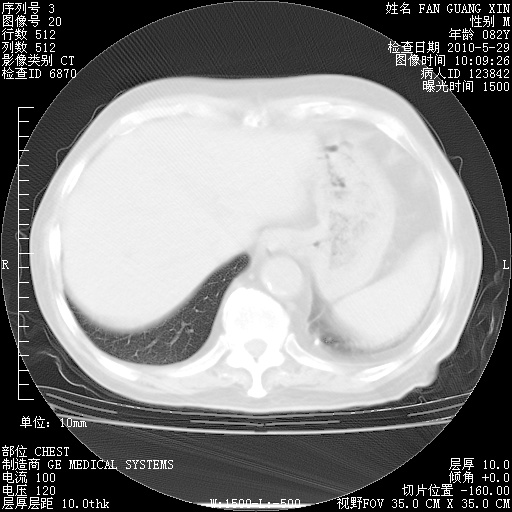

再治疗10天后的肺部CT

阅读此次胸部CT,肺间质渗出性改变较入院时有吸收。目前从体温、白细胞、中性分叶明显增高,肯定存在细菌感染(发生医院感染哦,若无消化道及泌尿系统等感染的依据,肺部感染可能大)。若你院头孢哌酮舒巴坦钠耐药率较高,同意你的方案,若48小时体温仍高,可考虑使用碳青霉稀类抗菌药物,同时可予超声雾化、注意滴数时加大液体量。白蛋白33.30g/L较低哦,需加强营养等支持治疗。